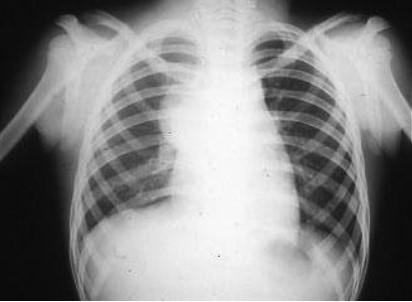

Common X-ray Findings: